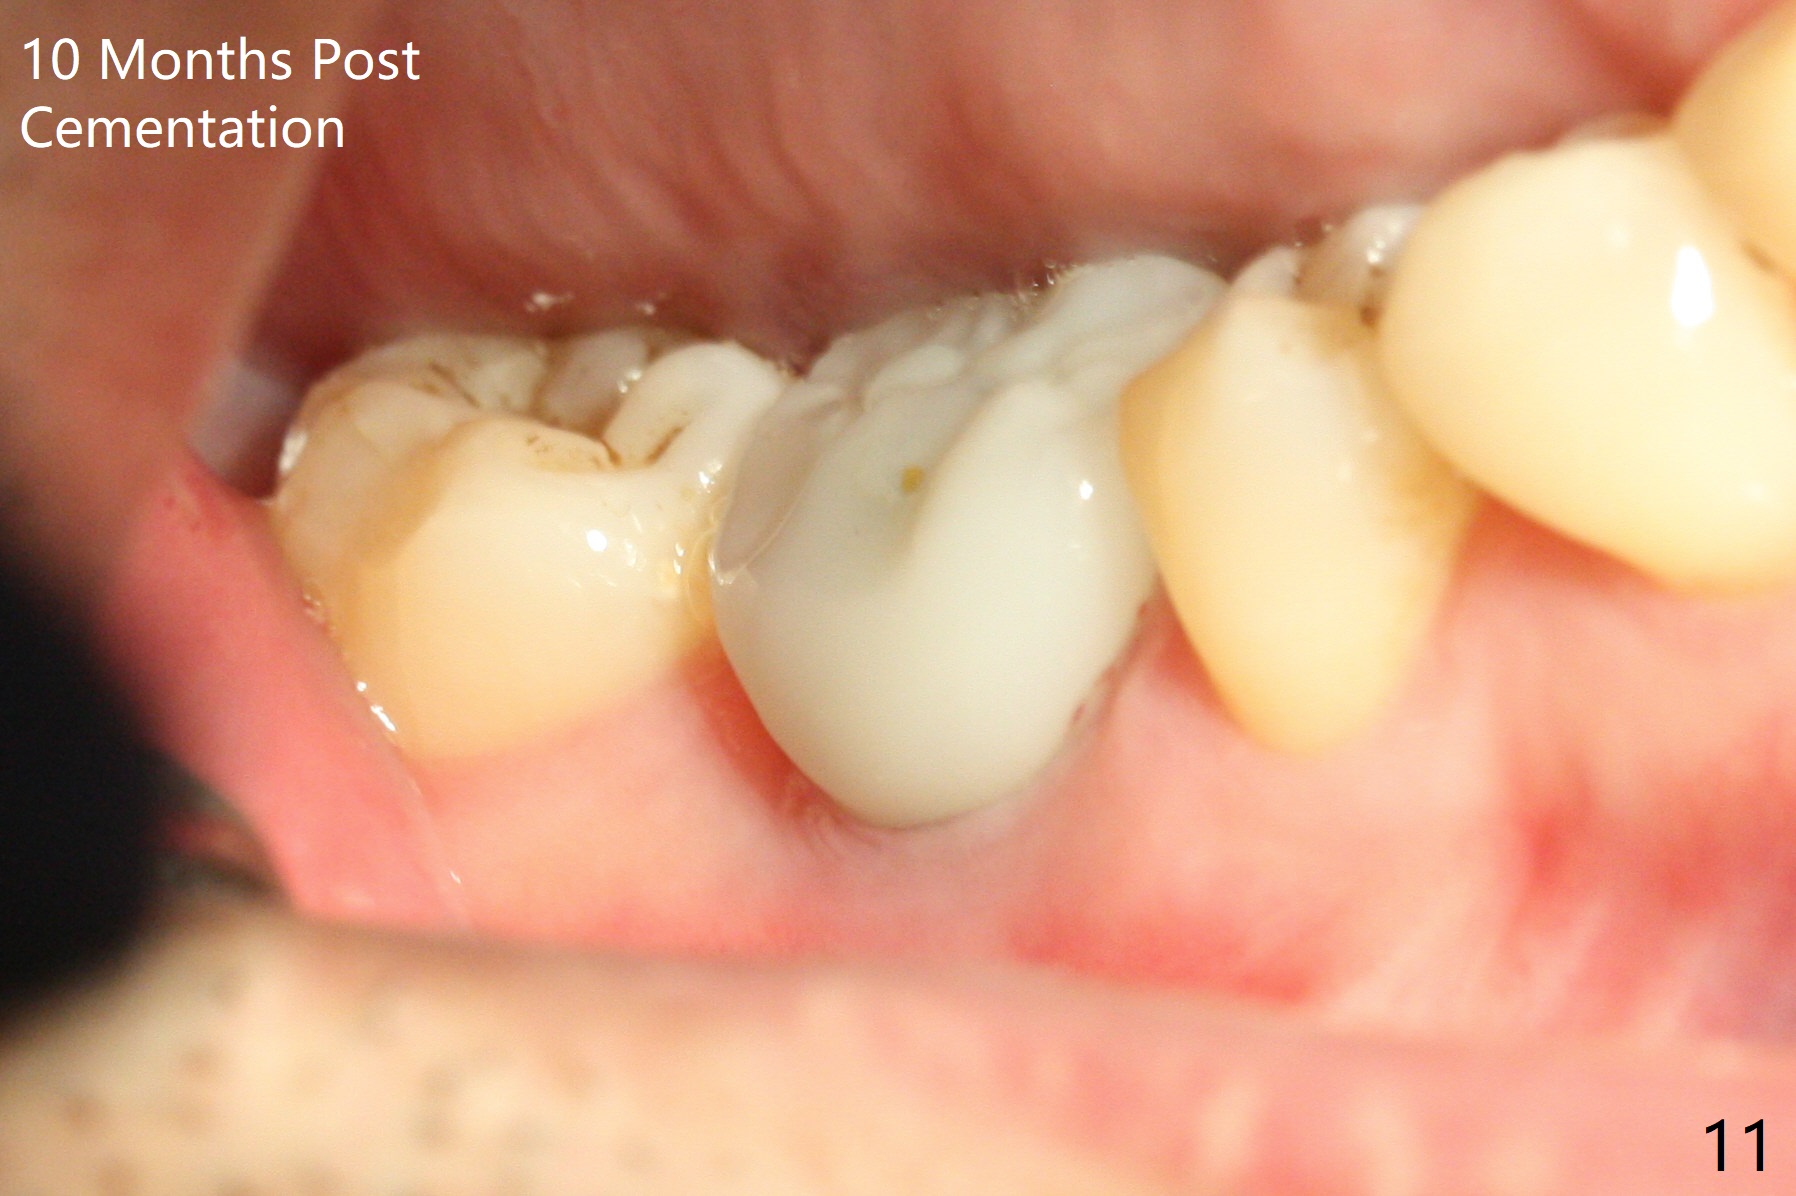

Fortunately no paresthesia is reported postop. Why is the Inferior Alveolar Canal not violated? Fig.7 is a coronal section of CBCT taken for a 40-year-old man at the lower 1st molar (at the septum). At the region, the Canal (brown circle) is close to the lingual plate (L). Because of severe bone loss of the lingual plate of this case (Fig.8 *), osteotomy is intentionally created buccal (green). The deep osteotomy may not contact the Canal, while the hemorrhage may stem from the medullary space (M in Fig.4,7). Bone morphology at the coronal end of the implant apparently changes 4 months postop, suggesting osteointegration (Fig.9). Impression is taken. Bone density around the implant at the crest seems to increase (Fig.10), while there is no soft tissue deficiency 10 months post cementation (Fig.11). The bone appears to regenerate toward the abutment, particularly distally, 14.5 months post cementation (Fig.12). Periimplantitis develops (bleeding on water pik and erythematous and tender buccal gingiva) 1 year 7 months post cementation (Fig.13,14). The 1st three threads are exposed (*). Bone graft with PRF and 6-month membrane or Cytoplast will be needed. Pain disappears 3 days of oral antibiotic. The gingiva looks healthy 1 month later when he returns for bone graft (Fig.15). But the lingual gingival cuff is not so healthy when the crown/abutment is removed (Fig.16 <). Bone graft is not done. For those patients with suboptimal oral hygiene, implants should be placed as low as possible, better with guide for precision.